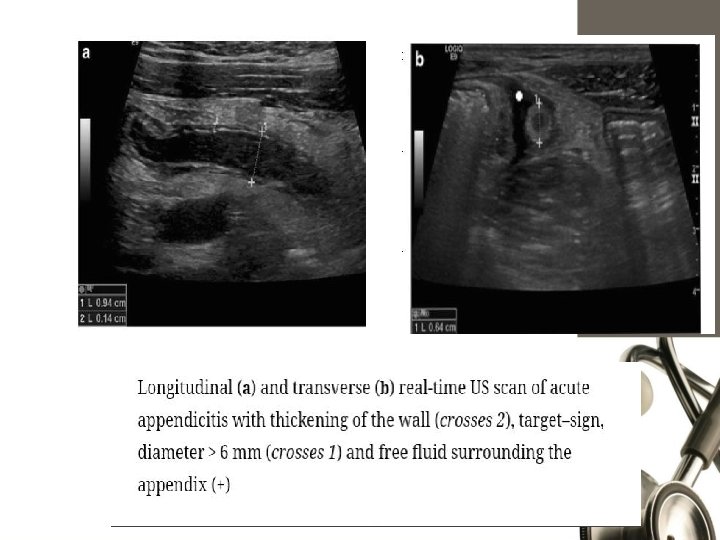

Graded Compression U/S Blind ending nonperistaltic bowel loop. Non compressible. Thickened wall>3 mm, lumen >6 mm. Presence of periappendicular fluid. Target sign. Appendicolith.

Ultrasonography. sensitivity of 55% to 96% and a specificity of 85% to 98%. (CT) scan 92% to 97% sensitivity, 85% to 94% specificity